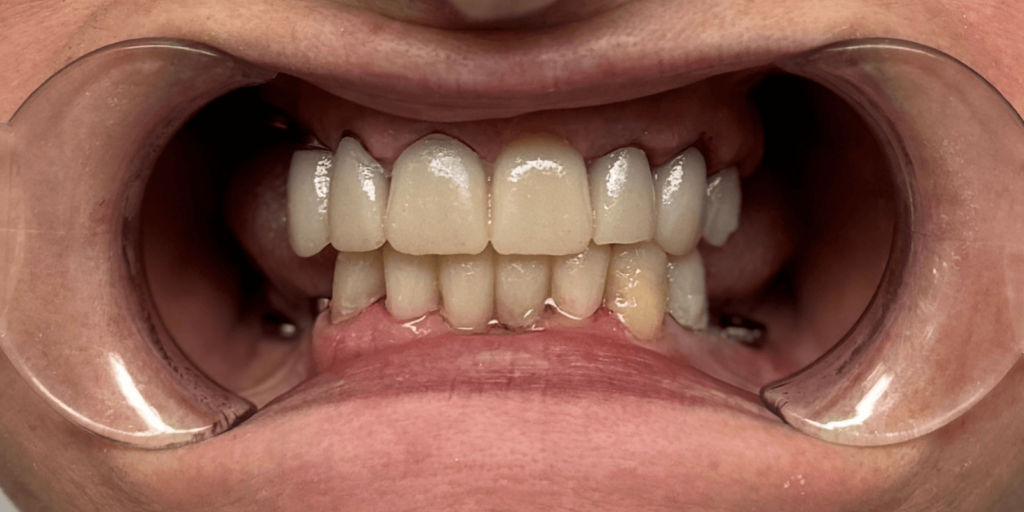

Итог

С момента первого визита прошло чуть менее трех месяцев. И когда пациентка в последний раз посмотрела в зеркало – мы увидели не просто улыбку. Мы увидели, как человек словно вернулся к себе.

Ее глаза засияли. Плечи расправились. Она начала смеяться громче. Ее жизнь изменилась не потому, что появились новые зубы, а потому, что исчезли все комплексы, которые годами мешали жить свободно.